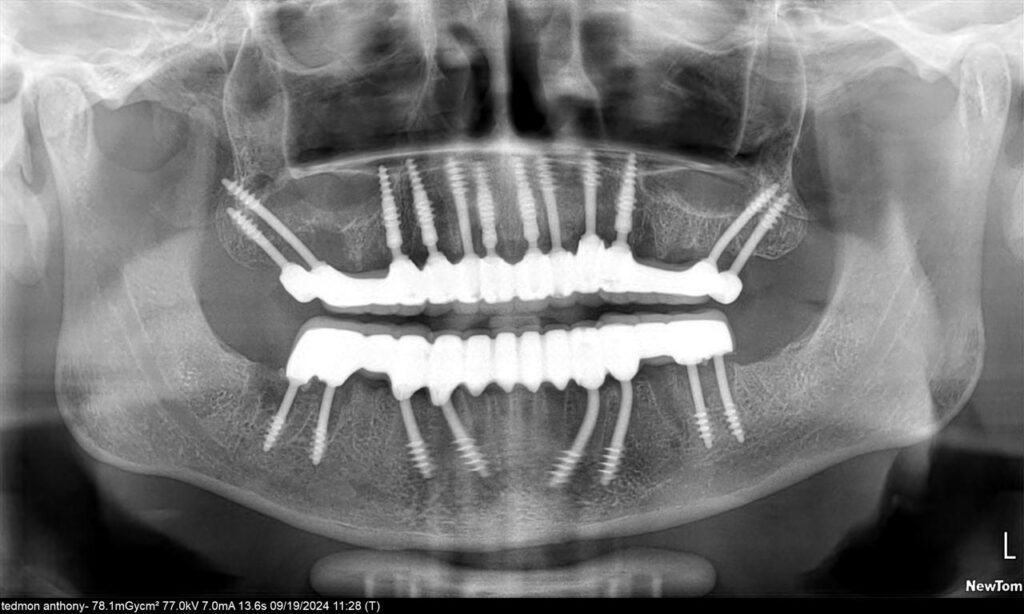

Your transformation begins with a clinical evaluation and radiographic analysis. After that, Dr. Vivek Gaur performs extractions of any decayed or loose teeth, thoroughly cleanses the site, and immediately places Corticobasal® implants into the stable cortical bone. Unlike traditional implants that require bone grafting or sinus lifts, these implants bypass such invasive interventions. Because the cortical bone remains structurally stable even in older or medically compromised patients, it provides a reliable foundation for immediate loading.

Once the implants are secured, advanced intraoral scanning and digital measurements are taken. These are swiftly transmitted to the clinic’s in-house laboratory where your customized prosthesis is fabricated using CAD/CAM technology. This seamless integration of diagnostics and manufacturing ensures precision, aesthetics, and function.